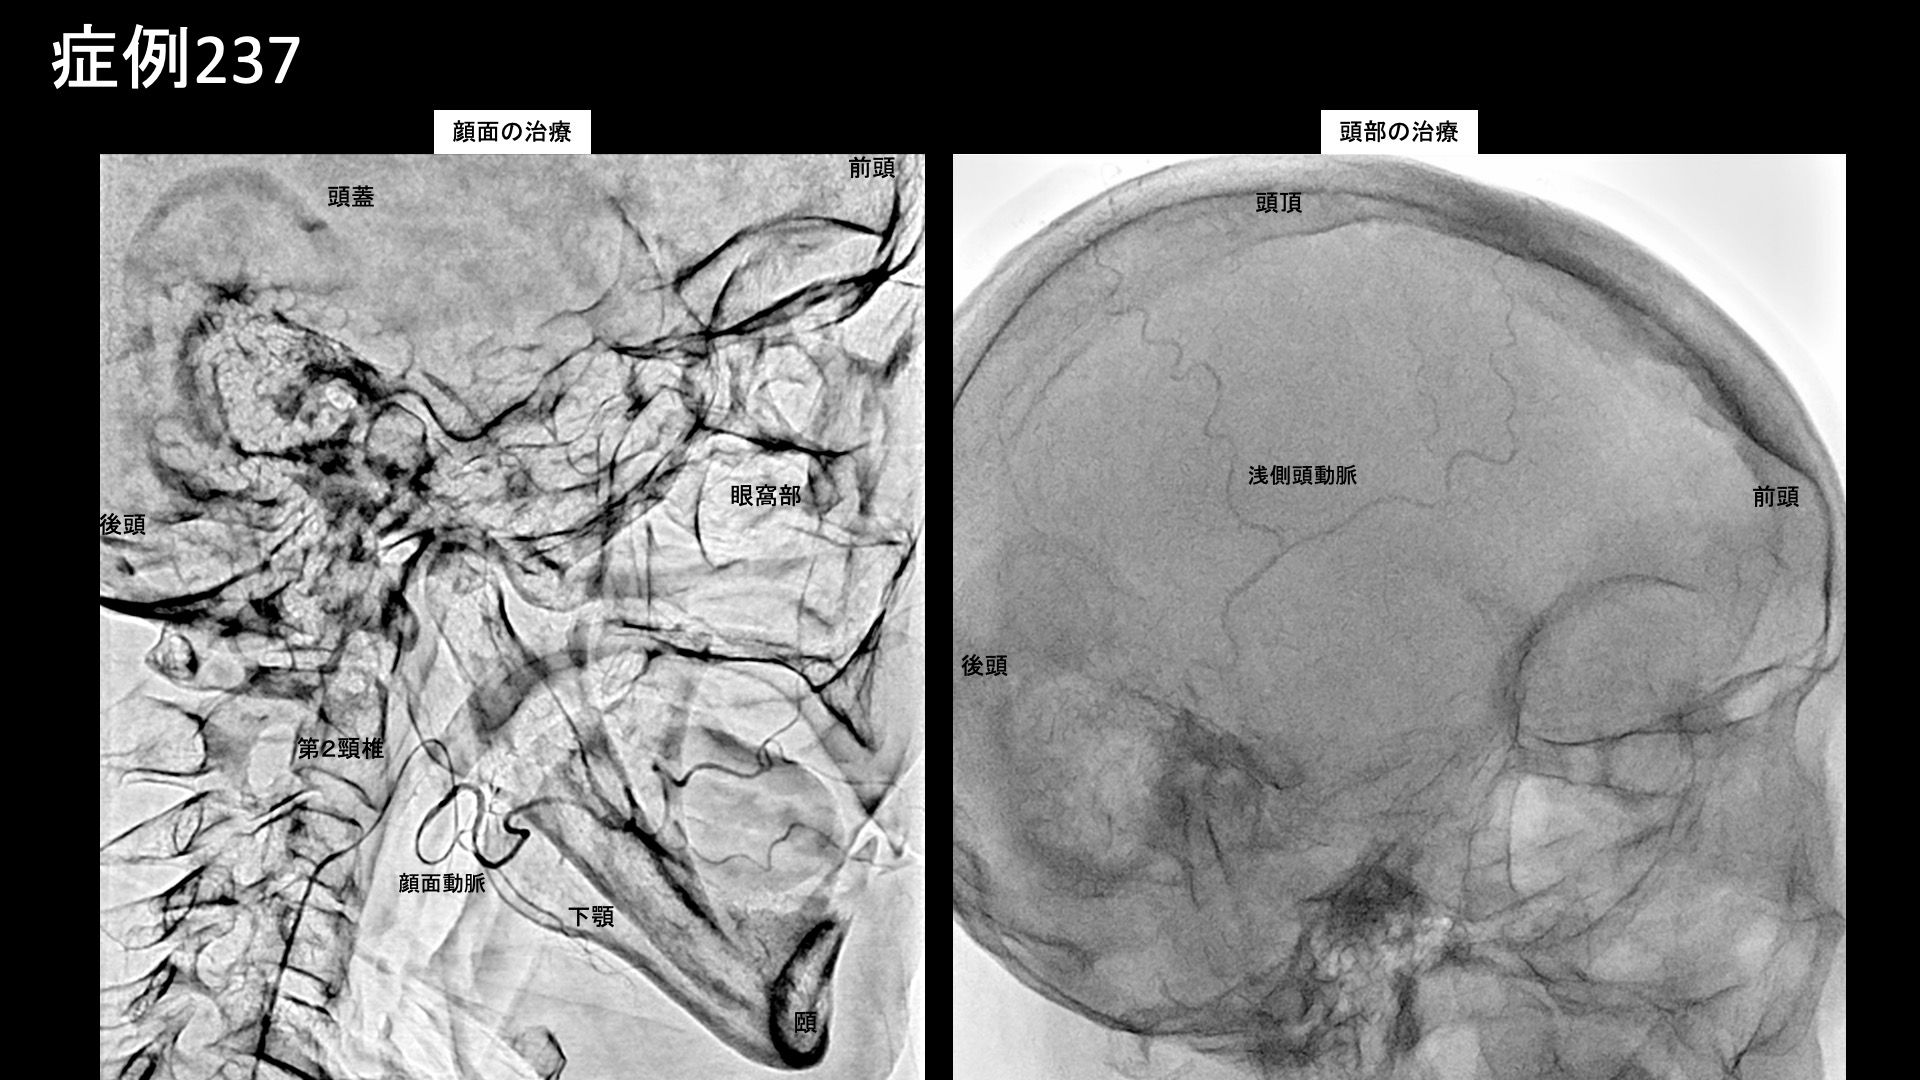

その他:帯状疱疹後など 【90代:女性】ここにできたら要注意!超高齢者に生じた頭部・顔面の帯状疱疹後神経痛(発症1ヶ月) (帯状疱疹後神経痛) 2025.09.16 鴨井院長による動画解説 受診までの経過 1ヶ月前に右顔面および頭部の帯状疱疹にかかりました。初めは頭部にポツっと一つ発疹ができ、その後右目の瞼が赤く水疱瘡のようになりました。アメナリーフ(抗ウイルス薬)を1週間服用しましたが、その後痒みから痛みに変わり、タリージェ(鎮痛薬)を処方されました。しかし効果はなく、ズキズキするような痛みが常にあり髪の毛を手で触れただけでも痛みがありました。夜は痛みで何回も目が覚めてしまい、寝不足のためお昼寝をするようになりました。痛みで食欲が低下して食べられなくなり、体重が2kg減りました。これまでは、家族から見ても活動的でしたが、発症してからは一歩も外に出ることなく、こたつに入っているようになりました。テレビも見ていられなくなってしまいました。痛みを忘れられる時間はありませんでしたが、入浴すると少しだけ楽にはなりました。頭部・顔面の帯状疱疹後神経痛は治りにくいと聞いていましたが、このままでは寝たきりにもなりかねないため、当院を受診されました。 診察時の所見 罹患部位が頭部・顔面であり、90歳代と高齢であることからは治療の有効性が懸念されるところですが、発症1ヶ月以内の早期に受診していただけましたので、治療による改善が十分期待されました。治療適応と判断し、モヤモヤ血管(病的新生血管)に対する運動器カテーテル治療(微細動脈塞栓術)を受けていただきました。 治療の所見 頭蓋表層に分布する浅側頭動脈、顔面に分布する顎動脈、顔面動脈などから治療を行いました。それぞれ再現痛を認めました。その他複数個所の治療を行い終了しました。 *再現痛とは、薬液投与時に普段の痛みが一定程度再現される現象です。責任血管の同定のための参考とします。 治療後の経過 治療当日の夜からすごく楽になり、嘘みたいと喜んでいました。1週間くらいで夜も良く眠れるようになったのですが、雪に見舞われて急激に寒くなった折に痛みが再燃しました。それでも当初の半分程度でした。治療後1ヶ月半、さらに改善が進みました。食欲が戻り、テレビも見られるようになりました。だいぶ活動的になってきました。頬や瞼がまだ少しピリピリするものの、7割方の症状が改善しました(3/10程度)。治療後3ヶ月、頭の痛みは消失しました。目の周りや頬の痛みが少しあるものの、ほとんど痛みなく過ごせることもありました。天気の悪い日は痛くなりますが、それでも3/10程度でした(全体的な評価としては、0-3/10程度)。活動的に過ごせているとのことでした。残存症状については少し長く時間をかけて解消されていくことが予想されます。 前述のように、頭部・顔面というより治りにくい罹患部位、超高齢ということを考慮すると非常に良好な経過でした。強い炎症を反映して、治療後すぐから改善が見られました。こじらせると日常生活が大きく破綻してしまいますので、本当に良かったと思います。とにかく、発症早期に治療を受けていただけたことが、良好な結果が得られた最大の要因です。もう3ヶ月でも遅れていれば結果は大きく異なっていたかもしれません。ご遠方から来院するだけでも大変だったことと思いますが、食欲低下、体重減少、睡眠障害など難治に陥る危険な徴候が重なってきた場合には要注意ですので、ご家族が後押しをして治療を決断できたことはなによりでした。前向きな気持ちで、まだまだお元気に過ごしていただけることと思います。 帯状疱疹後神経痛の詳しい病状説明はこちら 【40代:女性】9ヶ月苦しんだ四十肩の痛みが2週間でほぼ消失・・四十肩後遺症のモヤモヤ血管治療(四十肩、凍結肩、肩関節周囲炎) 前の記事 【80代:女性】新型コロナウイルス感染を契機に悪化した変形性腰椎症による腰痛/坐骨神経痛(新型コロナウイルス感染、変形性腰椎症、腰痛、坐骨神経痛) 次の記事